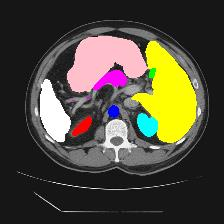

Medical image segmentation is one of the most fundamental tasks concerning medical information analysis. Various solutions have been proposed so far, including many deep learning-based techniques, such as U-Net, FC-DenseNet, etc. However, high-precision medical image segmentation remains a highly challenging task due to the existence of inherent magnification and distortion in medical images as well as the presence of lesions with similar density to normal tissues. In this paper, we propose TFCNs (Transformers for Fully Convolutional denseNets) to tackle the problem by introducing ResLinear-Transformer (RL-Transformer) and Convolutional Linear Attention Block (CLAB) to FC-DenseNet. TFCNs is not only able to utilize more latent information from the CT images for feature extraction, but also can capture and disseminate semantic features and filter non-semantic features more effectively through the CLAB module. Our experimental results show that TFCNs can achieve state-of-the-art performance with dice scores of 83.72\% on the Synapse dataset. In addition, we evaluate the robustness of TFCNs for lesion area effects on the COVID-19 public datasets. The Python code will be made publicly available on https://github.com/HUANGLIZI/TFCNs.

翻译:医学图像分解是医学信息分析的最根本任务之一,到目前为止已经提出了各种解决办法,包括许多深层次的学习技术,如U-Net、FC-DenseNet等。 然而,高精度医学图像分解由于医疗图像中存在固有的放大和扭曲,以及存在与正常组织密度相似的损伤,因此仍是一项极具挑战性的任务。在本文件中,我们建议TFCN(全面革命稠密网络的传输者)通过向FC-DenseNet引进ResLear-Transerferent(R-Transerfor)和Culvacial线性关注区(CLAB)来解决这一问题。TFCN不仅能够利用CT图像中更多的潜在信息来提取特征,而且还能够通过CLAB模块更有效地捕捉和传播语性特征和过滤非神经性特征。我们的实验结果表明,TFCN可以在Syapseion/SymblyDDS上以83CN-72 ⁇ 的分数实现状态。此外,我们在Synapse-DRIS数据设置上,我们还将评估CUTFTFI/LIS的可靠度。